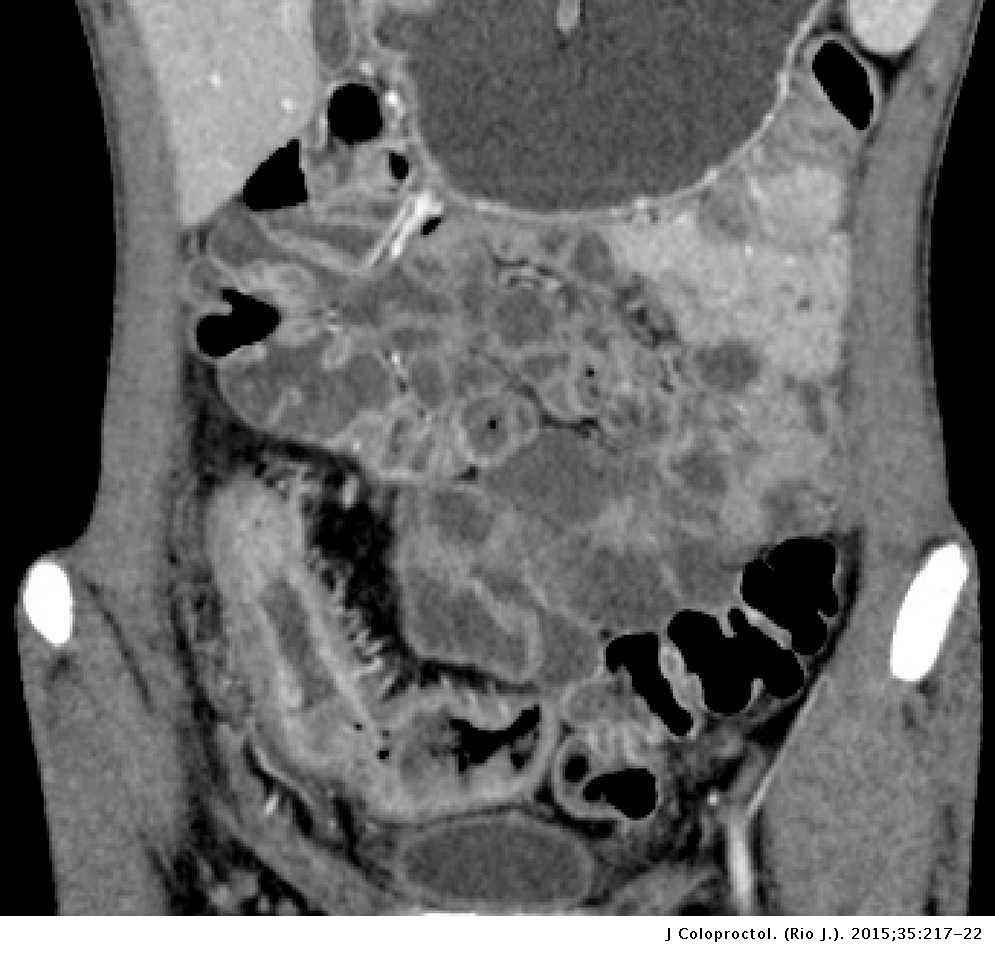

2️⃣ الأشعة

✳️ أشعة مقطعية

تطلب لتقييم الاجزاء المصابة في الجهاز الهضمي والكشف عن وجود اي نواسير في مرض الكرون

2️⃣ تضيق أو انسداد أو ثقب الأمعاء والتي قد تستدعي التدخل الجراحي